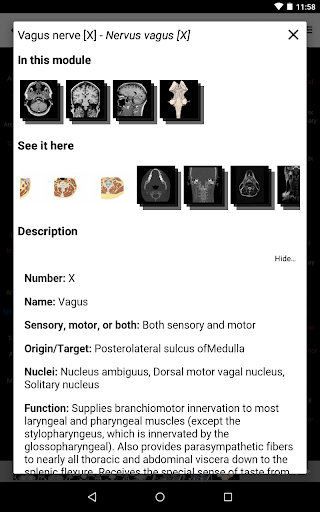

e-Anatomy memiliki lebih dari 26.000 gambar yang berisi serangkaian gambar dalam tampilan aksial, koronal, dan sagital serta radiografi, angiografi, gambar diseksi, bagan anatomi, dan ilustrasi. Semua gambar medis diberi label dengan cermat, lebih dari 967.000 label tersedia dalam 12 bahasa termasuk Terminologia Anatomica Latin.

*Peningkatan tampilan detail bagian anatomi untuk memudahkan identifikasi dalam gambar modul saat ini dan modul lainnya.

tampilan detail istilah terkait struktur anatomi sekarang ditampilkan

-Dalam tampilan detail struktur anatomi , pin sekarang menunjukkan struktur terkait di semua gambar yang ada